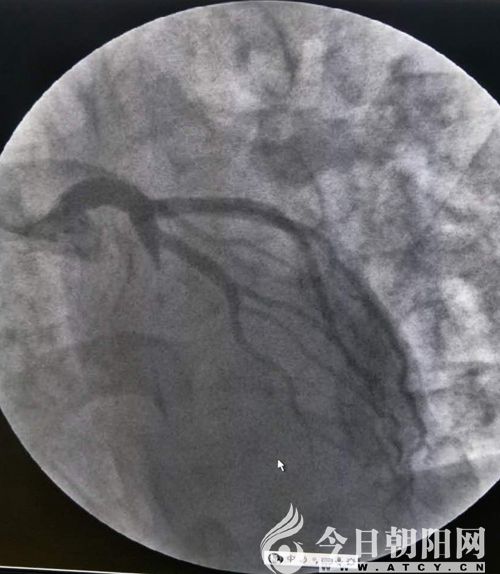

鄭某術(shù)后

兩名患者均屬于危急情況,相比之下,患者鄭某更重一些。單爽立即為鄭某實(shí)施手術(shù),術(shù)中見(jiàn)冠脈前降支支架內(nèi)100%狹窄,回旋支80%狹窄,血管內(nèi)布滿(mǎn)新發(fā)血栓,操作難度非常大。在導(dǎo)絲和球囊艱難通過(guò)后,依次進(jìn)行預(yù)擴(kuò)球囊及后擴(kuò)球囊于支架內(nèi)擴(kuò)張,前降支恢復(fù)三級(jí)血流,患者癥狀立即緩解。由于120急救中心在接診患者過(guò)程中,及時(shí)予以診斷,并開(kāi)通綠色通道、免費(fèi)心梗“一包藥”口服、建立左手靜脈通路等及時(shí)正確的處置,為患者的救治贏(yíng)得了時(shí)間。